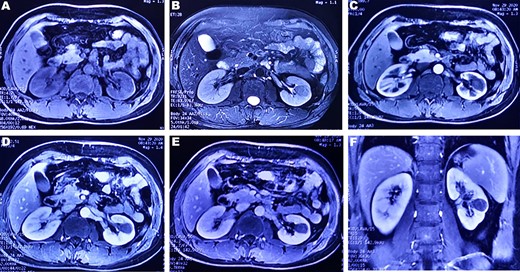

A 37-year-old male underwent a computed tomography scan (CT), which revealed a 2.5 × 1.9 cm slightly lower density ingrown mass in the lower pole of left kidney for 1 month. The patient was asymptomatic and had a history of kidney stones. The shape of the mass was regular, with unclear boundaries. Enhanced CT showed that the enhancement of the mass was lower than that of the surrounding renal parenchyma (Fig. 1). On magnetic resonance imaging (MRI), a circular abnormal signal was detected in the cortical medullary area of left kidney, with an equal signal on T1WI and a slightly low signal on T2WI (Fig. 2A and B). The enhanced MRI scan showed no obvious enhancement in the cortical and medullary phases and a slightly dotted high signal in the excretion phase (Fig. 2C–F). The mass was a space-occupying ingrown lesion with insufficient blood supply. Patients underwent laparoscopic partial nephrectomy and received no postoperative therapy. After the tumor was incised, a 2.3 × 2 cm soft mass that was grayish-white and slightly grayish-yellow was found with clear boundary. Histology (hematoxylin and eosin staining) results showed that the tumor was composed of elongated tubules arranged in parallel. The tubules lined with cuboid and spindle cells set in a small amount of myxoid matrix (Fig. 3A). Most of the tumor cells were round, a few were spindle and elliptical, with eosinophilic nucleoli. Mitotic figures were rare and the atypia is not obvious. Obvious foamy macrophage aggregates could be seen in some areas (Fig. 3B). Immunohistochemical results were as follows: CK7(+), P504S (+), PAX-8(+), CD10(−) (Fig. 3C–F). The Ki67 stain showed proliferation rates up to 5%. The pathological result demonstrated left renal mucin-poor MTSCC. We performed next-generation sequencing (NGS) for case, and the result showed that the tumor mutational burden was 2.74 mutation/Mb. RET gene mutation was considered as a mutation of uncertain significance. The detection of multiple genetic polymorphism sites of tumors shows that it may be slightly sensitive to some chemotherapeutics like gemcitabine. PD-1/PD-L1 immunotherapy may not benefit the patient. The patient was followed up for 8 months after surgery. No evidence of metastasis or recurrence was found.

CT plain scan and enhanced scan of mucus-poor MTSCC. (A) CT scan showed a low-density mass in the lower pole of the left kidney (arrow), unclear boundary, swelling growth in kidney; (B) enhanced CT scan of corticomedullary phase shows tumor mild homogeneous enhancement, (C) nephrography phase, (D) renal excretion phase.